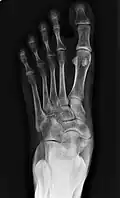

Radiographie du pied montrant un os naviculaire accessoire

Un os naviculaire accessoire est un os accessoire du pied qui se développe parfois anormalement devant la cheville vers l'intérieur du pied. Cet os peut être présent dans environ 2 à 14 % de la population générale et est généralement asymptomatique[1],[2],[3]. Lorsqu'il est symptomatique, une intervention chirurgicale peut être nécessaire.

Les radiographies sont généralement commandées pour confirmer le diagnostic. S'il y a une douleur ou une inflammation en cours, une IRM ou d'autres tests d'imagerie avancés peuvent être utilisés pour évaluer davantage la condition.

Images radiologiques